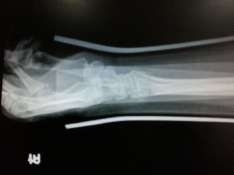

桡骨远端骨折整复后

一、中医手法整复

二、现代手术治疗